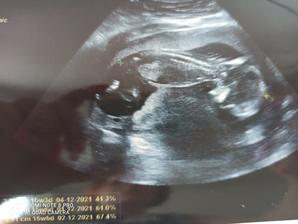

13.4 1. kontrola u doktora, pan doktor viděl počínající srdeční akci, byla vidět i mini housenka s bublinou, na fotce pro manžela nevidím nic😅, ale důležité je, že velikost odpovídá, další kontrola 4.5

4.5 miminko je krapet menší, ale máme průkazku, kontrola za 14 dní, máma nervák má spodní tlak 118😅